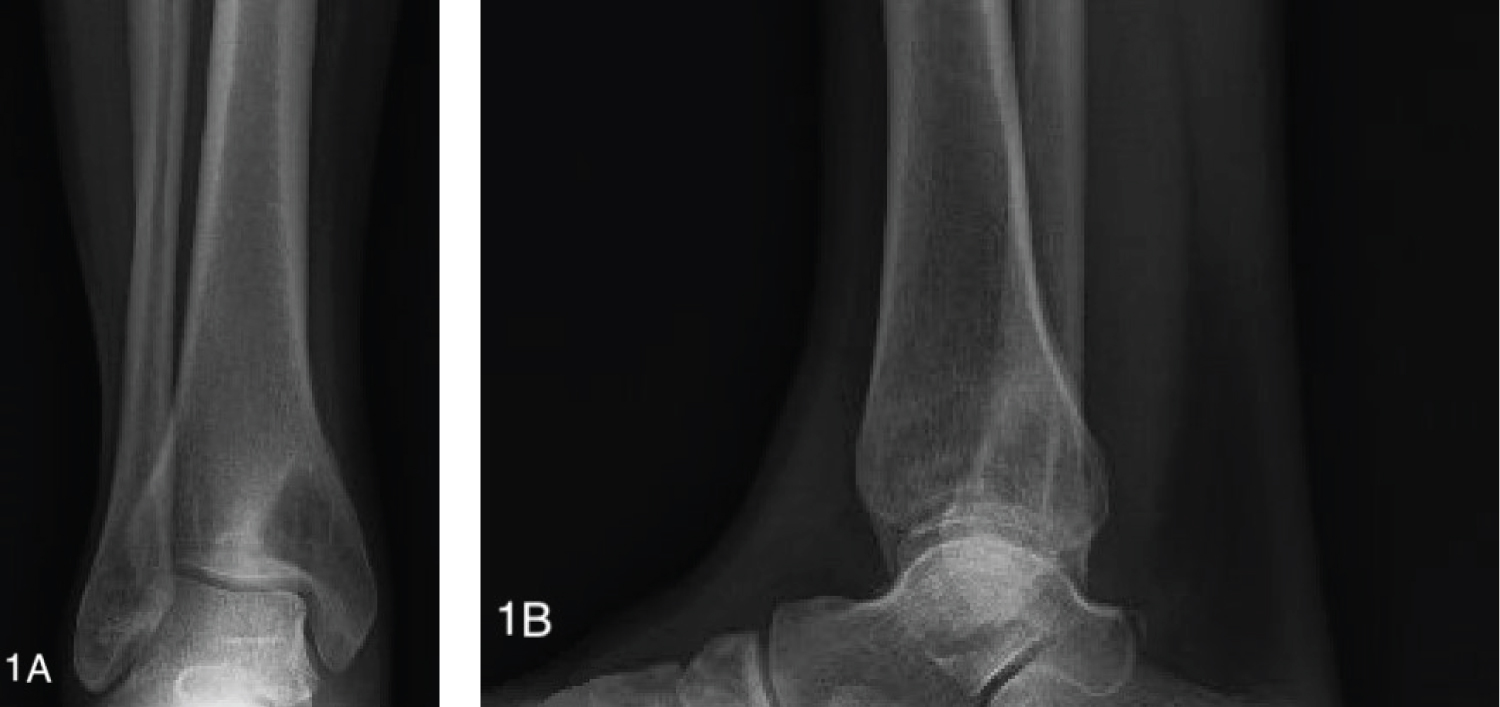

Conventional radiographs demonstrated a lytic bony lesion in the right medial malleolus (Figure 1). Magnetic resonance imaging (MRI) demonstrated a contrast enhancing marrow replacement lesion in the medial malleolus as well as the lateral calcaneus (Figure 2). Whole body bone scan demonstrated multiple lesions throughout the bilateral lower extremites (Figure 3).

Figure 2: MRI reveals enhancing marrow replacing lesions of the medial malleolus and lateral calcaneus without significant cortical or soft tissue involvement. Axial T2 FSE (a), axial T2 FSE (b), coronal T2 FSE (c), and coronal T1 PG FS (d). View Figure 2